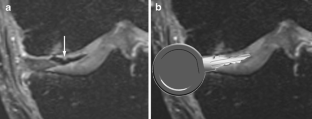

A total of 914 consecutive exams from 875 patients (524 men; mean age, 35 years) were reviewed. Vacuum phenomenon was found in 12 patients (prevalence 1.3%). In six (50%) patients, VP mimicked a meniscal tear, with four cases simulating a torn medial discoid meniscus. The VP signal was not easily differentiated from meniscal signal on most sequences in most cases (9/12). Gradient-recalled echo (GRE) localizer images proved most definitive, with 3D SPACE images the next most effective. Fast spin echo (FSE) images were only occasionally able to differentiate VP from meniscus.

Rarely recognized on MR, VP can mimic meniscal pathology, potentially leading to inappropriate surgery. Because differentiation of VP from the meniscus is challenging on FSE at 3 T, radiologists should become familiar with the appearance of VP and review GRE localizer or 3D images carefully to avoid misinterpretation.